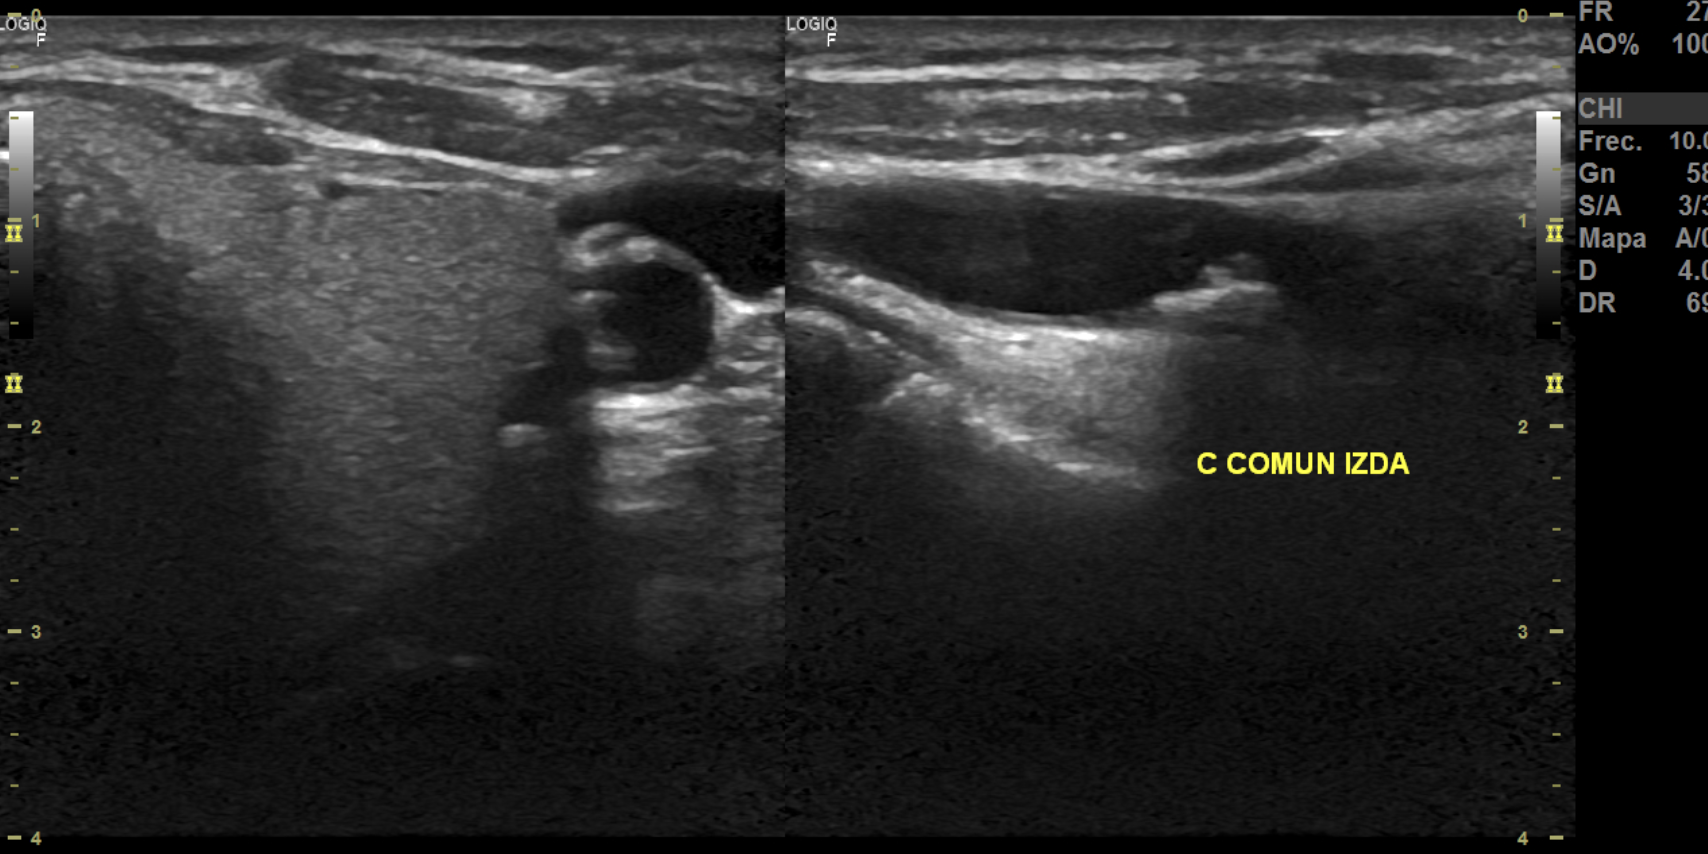

Hallazgos ecográficos

La ecografía Doppler carotídea realizada en AP mostró placas hiperecoicas y calcificadas en ambas carótidas comunes, con estenosis bilateral de aproximadamente 20% del lumen. Carótidas externas e internas permeables y morfología normal.

Hallazgo incidental de placas ateroscleróticas subclínicas. Diagnóstico especializado hospitalario: ateromatosis de carótida común bilateral.